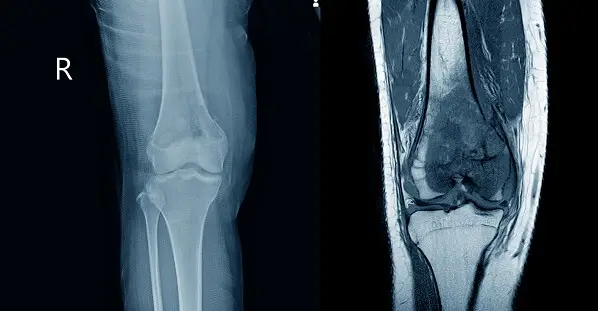

Diagnostic

Diagnosticul incepe cu efectuarea anamnezei pentru a identifica simptomele bolii si potentialii factori de risc.

Ulterior se efectueaza un examen clinic complet, care poate identifica formatiunea tumorala si alte semne ale bolii.

Biopsia este necesara pentru confirmarea malignitatii dar si tipului specific de sarcom.

Imagistica prin rezonanta magnetica a regiunii afectate este cea mai buna optiune pentru caracterizarea tumorii.

Computer tomografia este utilizata pentru a identifica metastazele, dar in unele cazuri poate sa fie necesara efectuarea unui PET-CT.